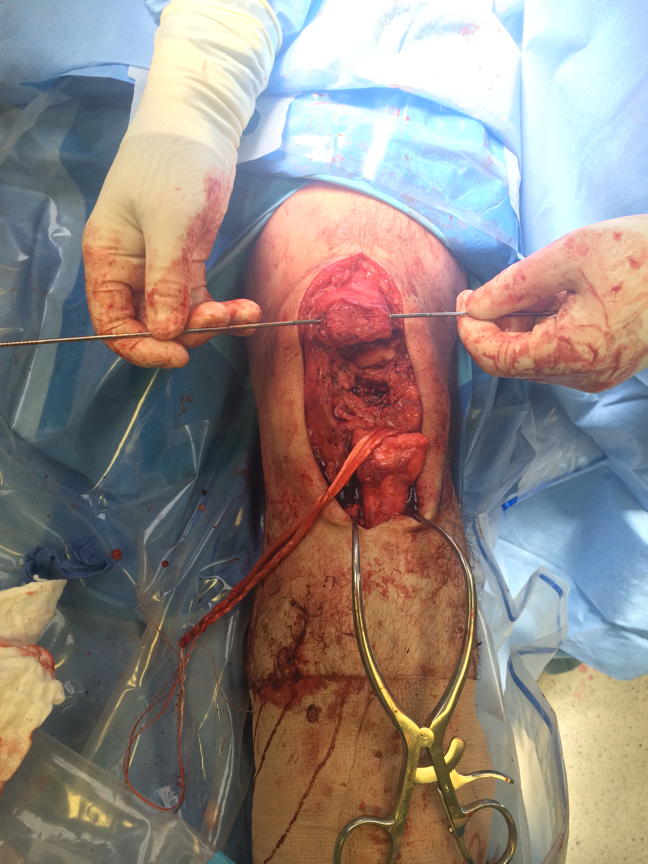

Technique

Problem

- avoid baja caused by overtightening patella tendon

- drape patient in such a way so as to palpate other PT

- compare patella heights at end of case

1. Tendon torn off patella

Multiple Bunnell / Krackow Sutures to Patella Tendon

- 2 non absorbable

- drill holes through patella ( 3 - 4)

- pass sutures and tie

- can augment with box fibrewire

Can reinforce with box wire loop

- large gauge wire 18G

- drill hole in tibial tuberosity

- transverse drill hole in patella

- pass in square and tie

- protects patella tendon

- problem is will break / irritate / need removal

- only do if concerned re repair

Test repair at end of case

- should be able to do some limited ROM

1. Semitendinosus autograft

- leave semitendinosus attached distally

- pass through distal pole patella

- reattach to tibia on lateral side